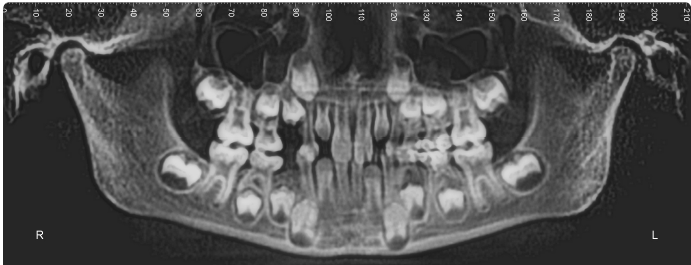

i-CAT 3D Imaging SystemOur i-CAT 3D Imaging System provides precisely accurate 3D views to analyze teeth, roots, TMJ, airway, and sinuses without magnification or distortion in less than 5 seconds. With more information than is rendered from a more traditional x-ray, we are able to provide treatment that is beyond straight teeth.

WHAT DO WE SEE WHEN WE LOOK AT YOUR ICAT 3D IMAGE?

DENTAL DEVELOPMENT

In the i-CAT, we are able to see all the primary (baby) and permanent (adult) teeth. We are able to see if there is enough space for the developing teeth to come into proper position. Sometimes, baby teeth that have not fallen out yet may be blocking the adult teeth from erupting. When we see this, we are able to intervene early to make space allowing the teeth to erupt properly.

POSITION OF THE TEETH AND ARCHES

With the images taken from the iCat we are also able to map out the position of the teeth. We are also able to map out the Maxilla(the upper arch) and the Mandible (the lower arch) and compare their relationship to each other. This map can help us determine what appliances will help you achieve your orthodontic treatment goals.